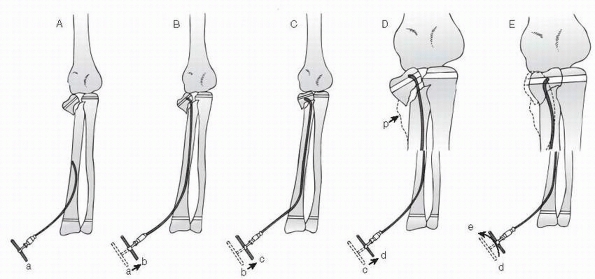

proposed reducing severely tilted radial neck fractures with an

intramedullary wire passed from the distal metaphysis. A report 13

years later61 demonstrated the

effectiveness of this technique. A wire is inserted into the medullary

canal through an entrance hole in the distal metaphysis (Fig. 11-22).

Once the wire reaches the fracture site, the angulation at the tip

enables it to engage the proximal fracture site at the neck. Once

engaged, the wire is twisted to reduce the head and neck fragment. This

technique has produced results superior to open reduction with fewer

complications.32,98

FIGURE 11-22 Intramedullary pin reduction. A. The insertion point for the curved flexible pin is in the metaphysis. B. The curved end of the rod passes in the shaft and engages the proximal fragment. C. Manipulation of the rod disimpacts the fracture. D,E.

Once disimpacted, the head fragment is rotated into position with the intramedullary rod. (From Metaizeau JP, Lascombes P, Lemelle JL, et al. Reduction and fixation of displaced radial neck fractures by closed intramedullary pinning. J Pediatr Orthop 1993;13:355-356; with permission.) |